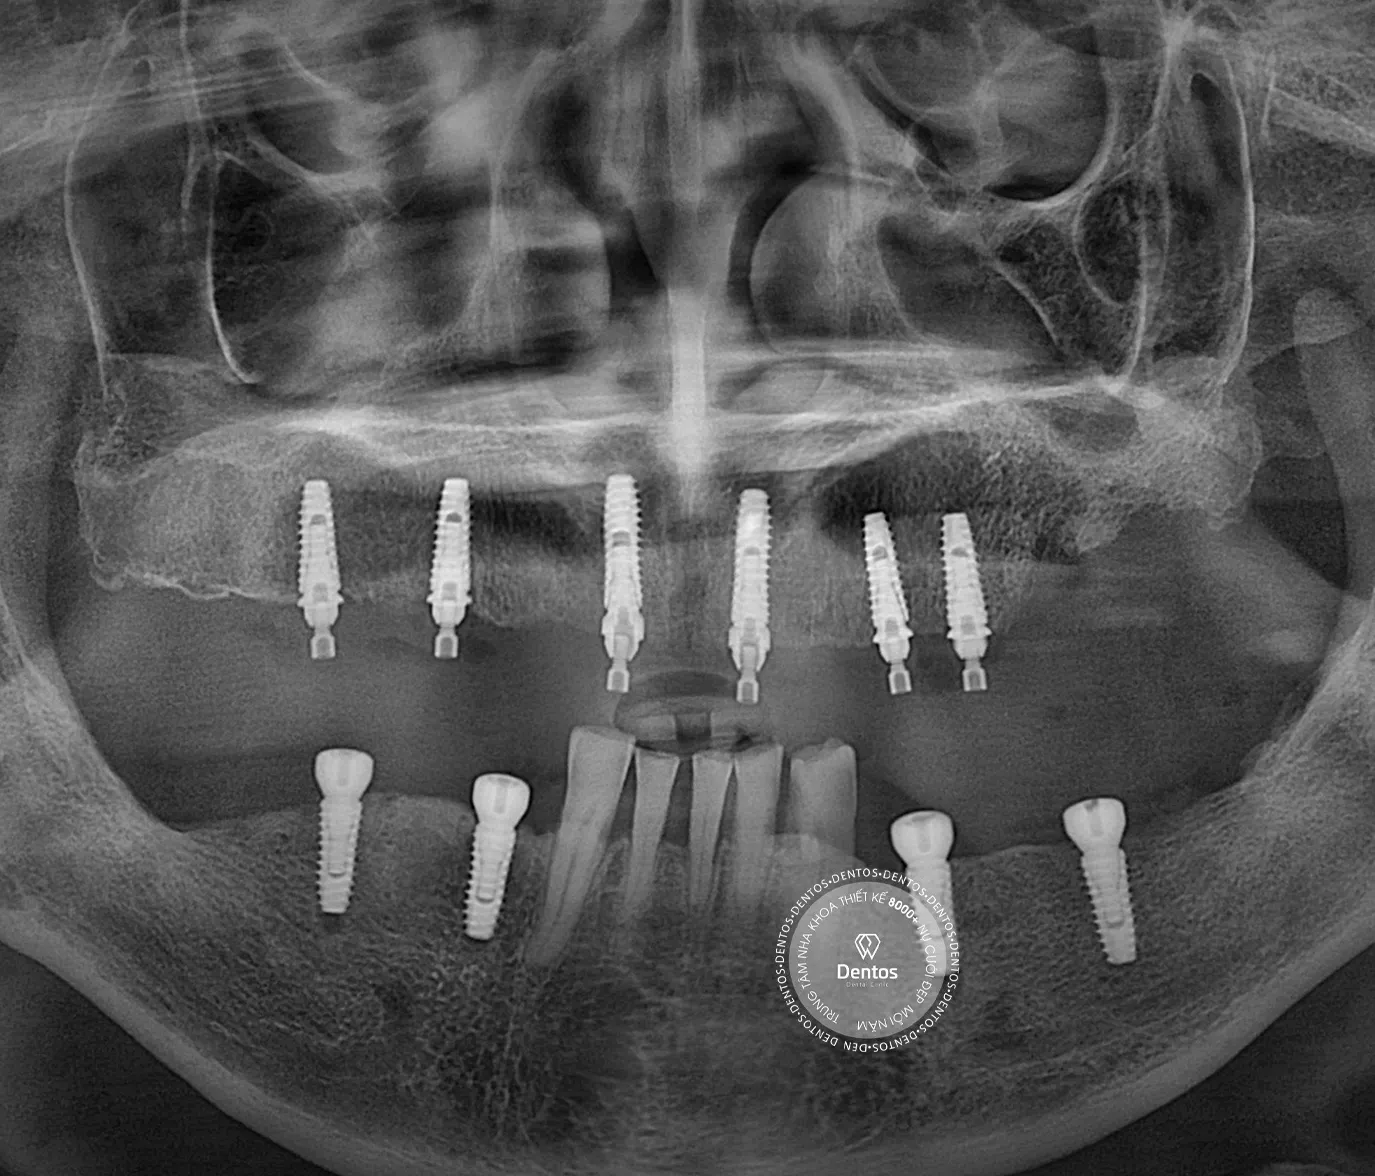

Trụ Tekka Implant Pháp là sản phẩm đang được sử dụng rộng rãi trên thị trường với tỉ lệ thành công lên tới 99%. ...

Trồng răng sứ là giải pháp phục hình răng rất phổ biến và hiệu quả trong lĩnh vực nha khoa, giúp khôi phục lại chức ...